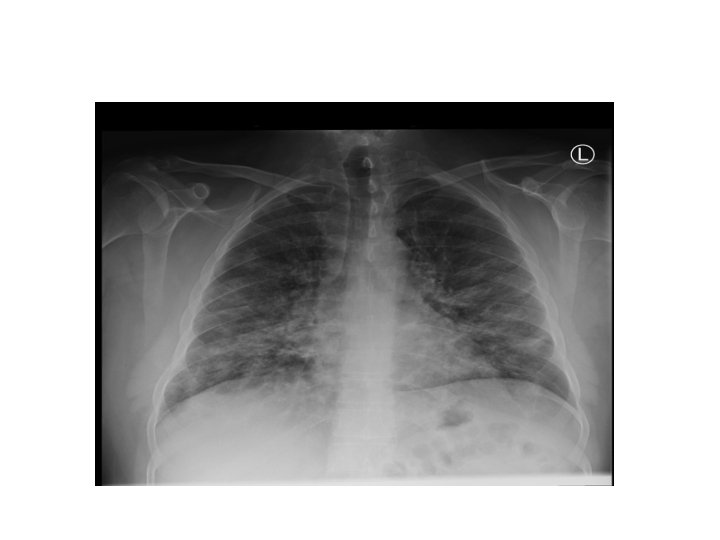

Lobar Pneumonia and Bronchopneumonia • Lobar pneumonia is usually unilateral and involves a lobe • Bronchopneumonia is usually bilateral with patchy reticulonodular opacities.